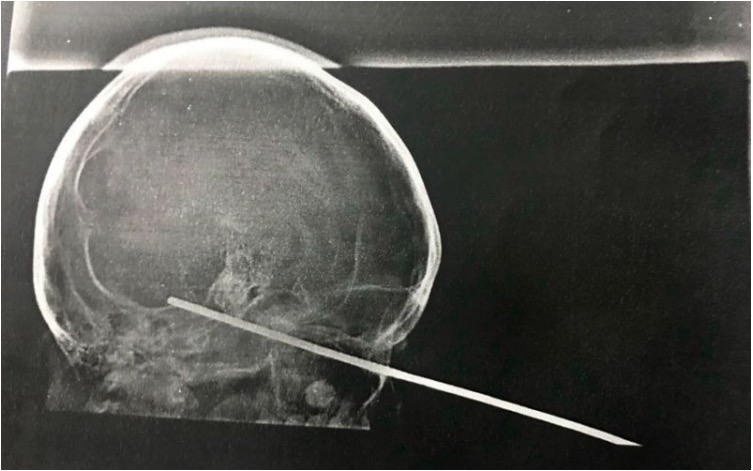

Uma foto do raio-x, divulgada pela assessoria da Santa Casa de Misericórdia de Itabuna, mostra a posição do espeto na cabeça da criança.

O incidente ocorreu no último domingo, 22, quando Rian brincava com o espeto e acabou tropeçando. Com a queda, o objeto perfurou seu olho e acabou atingindo o cérebro.

Após passar por exames, foi constatado que Rian não sofreu sequelas. "O espeto atingiu uma área, até então, letal. A própria equipe médica considera o caso como um milagre", ressaltou o hospital, por meio da assessoria de comunicação para a UOL. Ele apenas apresenta um desequilíbrio na pálpebra, mas sua visão permanece normal.